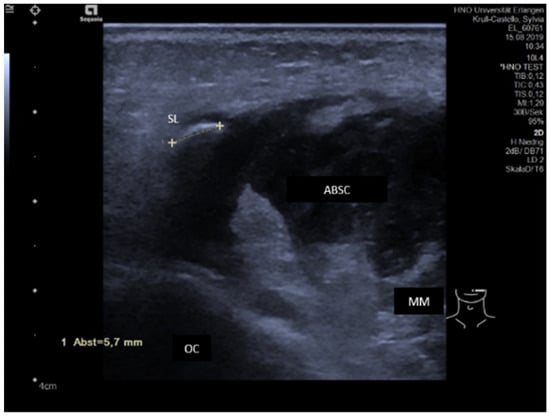

3.3.1. Acute or Subacute Primary Non-Obstructive Microbial Sialadenitis

3.3.2. Obstructive Sialadenitis Caused by Sialolithiasis

3.3.3. Non-Sialolithiasis-Caused Unspecific Sialadenitis with Sialodochitis and/or Duct Stenosis with Primary or Secondary Obstruction